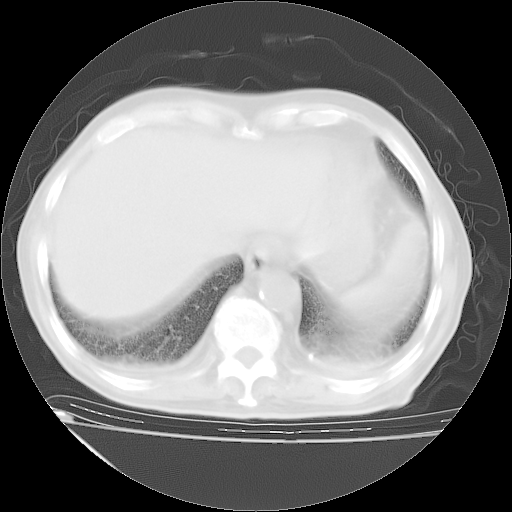

补充下:5月9日胸部CT:似乎已见双下肺胸腔积液了,鉴于目前有下肢水肿,肝功示:白蛋白低,应注意多浆膜腔积液(漏出液可能大?),需注意!

甲强龙80mg/日+抗结核治疗(异烟肼+利福霉素+乙胺丁醇)10天。复查肺部CT。

治疗10天肺部CT